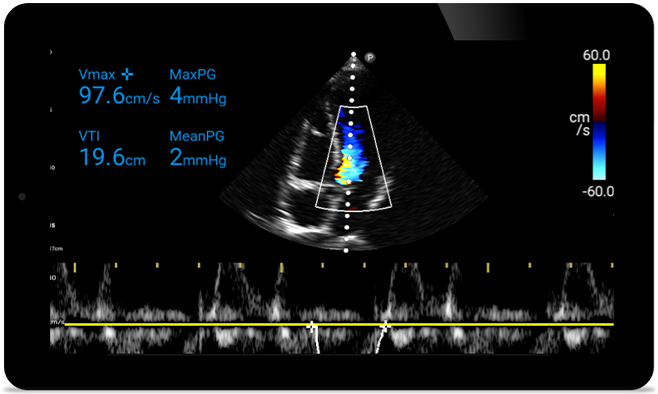

When seconds count, portable ultrasound can make the difference. Lumify can provide the high-definition imagery you need whenever and wherever you need it.

Lumify S4-1 broadband phased array transducer

• 4 to1 MHz extended operating frequency range.

• 2D, Color Doppler, M-mode, advanced, XRES and multivariate harmonic imaging.

• High-resolution imaging for abdominal and cardiac applications: cardiac, OB/GYN, lung, abdomen and FAST imaging preset optimizations.